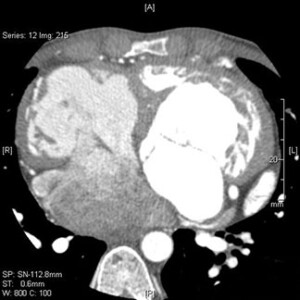

The CT Scanner, or the Diagnostic and Wellness Center, has been a major center of research and development in the field of coronary artery calcium and cardiac computed tomography angiography (CCTA). Helmed by Dr. Matthew Budoff, it holds one of the most experienced research teams in the world and has been performing CT interpretation and has paved the way for the role of CCTA in the noninvasive diagnosis of coronary artery disease and anatomical visualization for over 20 years.

As the Cardiology fellow on Advanced Imaging at Harbor-UCLA, you can:

- Participate in the acquisition and interpretation of coronary CTAs, over 100 of which are done monthly

- Gain exposure to multimodality advanced imaging, including when performed by Dr. Jina Chung

- Correlate findings from echocardiography, CT, angiography and cardiac MRI through image acquisition, case interpretation, and teaching conferences